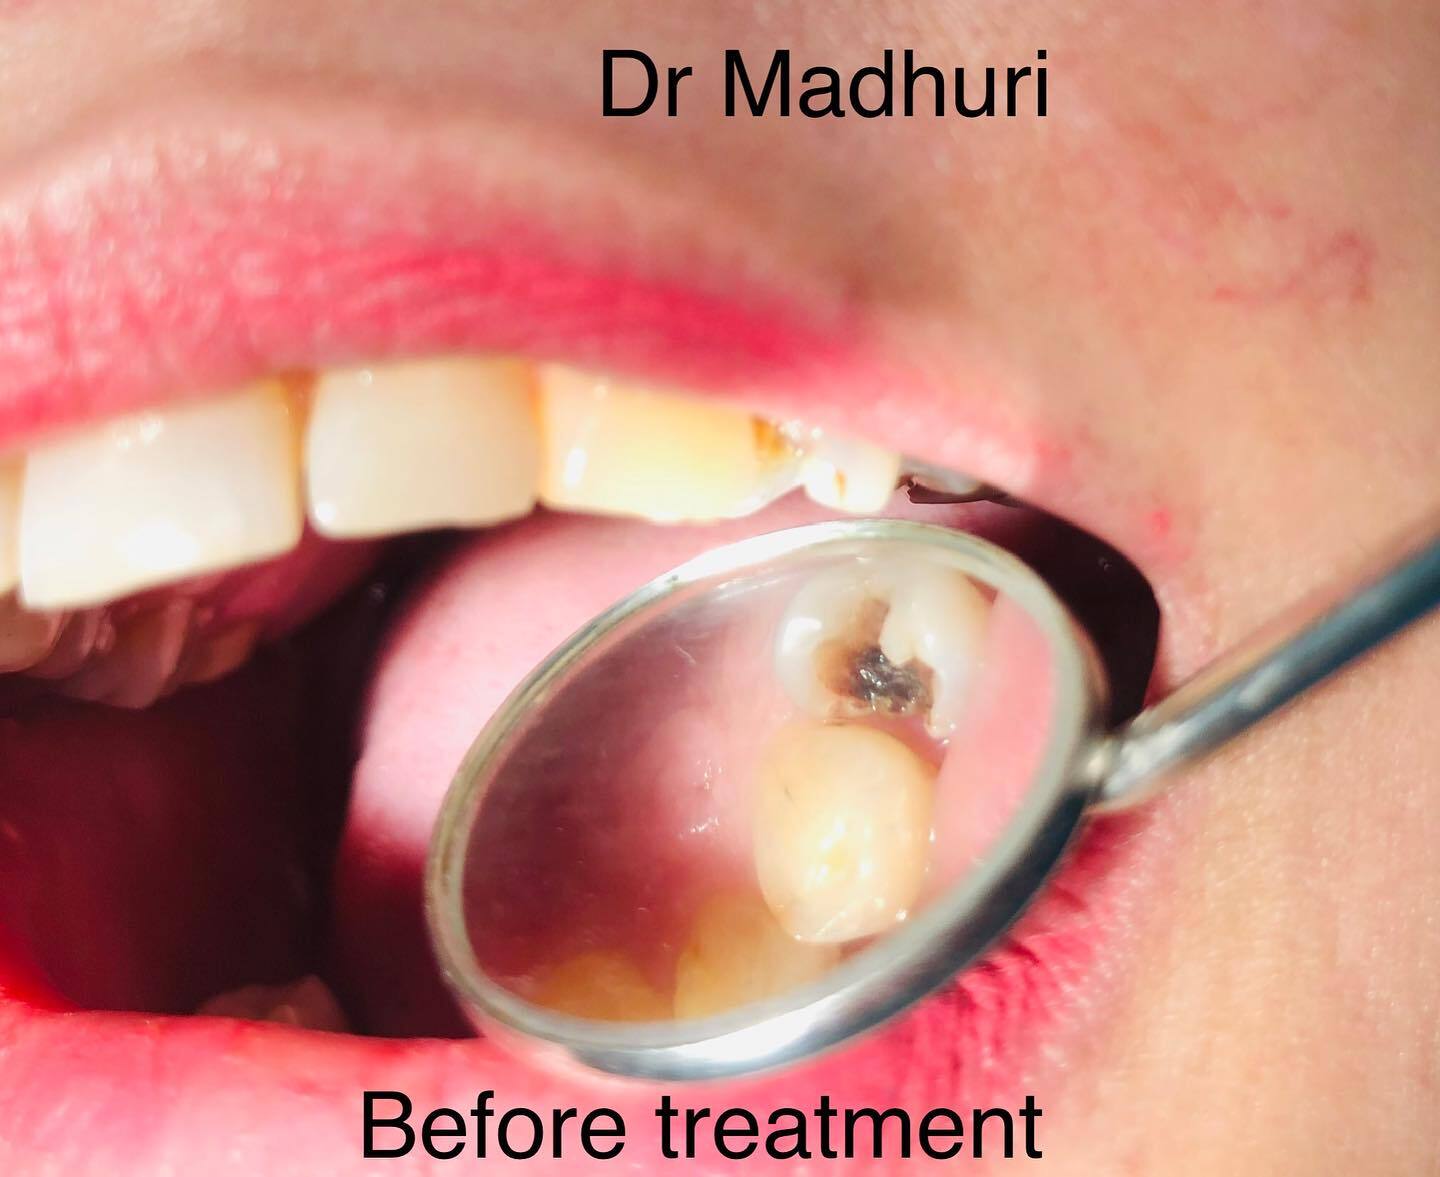

Explore Our Clinical Dental Gallery

Welcome to our official treatment gallery, showcasing the real results, smile transformations, and advanced dental care delivered by Dr. Madhuri. We believe that a picture is worth a thousand words when it comes to the art and precision of modern dentistry. Review our comprehensive visual portfolio below to see how our dedicated care helps patients achieve healthy, beautiful, and confident smiles.